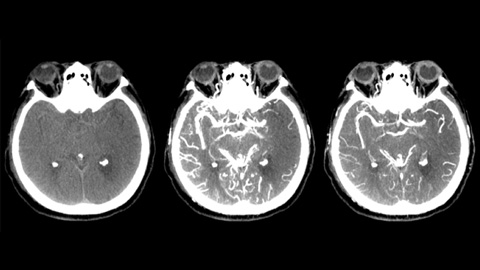

XperCT ohne Kontrastmittel unterstützt die Erkennung früher ischämischer Veränderungen. XperCT hilft in der Frühphase der Kontrastmittelanreicherung bei der Ermittlung der proximalen Okklusion. XperCT unterstützt in der Spätphase der Kontrastmittelanreicherung bei der Erkennung von Kollateralen.

Die Anzeige der XperCT Dual Volumina der Früh- und Spätphase nebeneinander verbessert die Erkennung der Penumbra und ermöglicht die Darstellung der kollateralen Füllung.